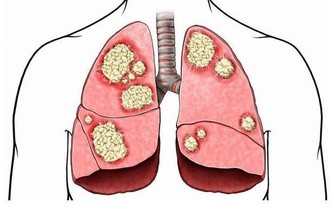

當膀胱癌到達第4階段時,原始腫瘤經常生長並推動膀胱壁。癌細胞可能已經擴散到靠近膀胱的器官或更遠的器官,例如肝臟或肺部。於是其症狀可能包括: